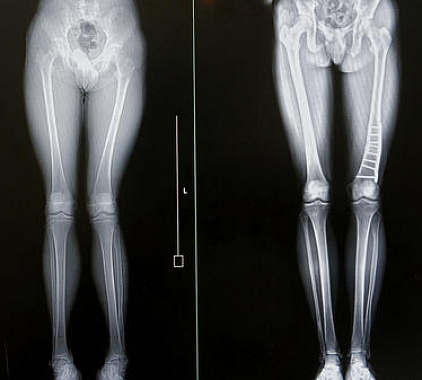

Фотогалерея

- мониторирование эффекта хирургического вмешательства, выполненная операция;

- оценка срастания переломов;

- отслеживание динамики имеющихся заболеваний;

- мониторинг успешности терапии.